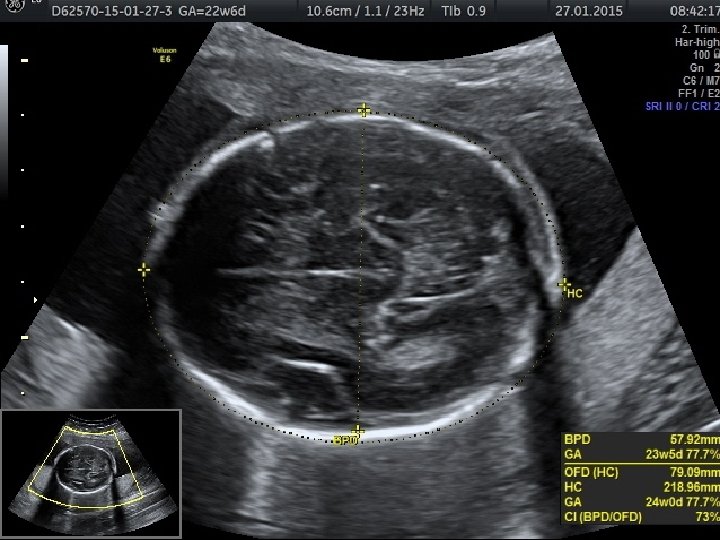

• Anormal biyometri saptanan hastalarda anormal fetal büyümenin fetal, plasental veya maternal nedenlerinin belirlenmesi amacıyla klinik ve ultrasonografik muayene yapılması gerekir. • Tahmini fetal ağırlığın saptanması için birçok formül önerilmiştir. • Bu formüllerin birçok parametre içermesine (biparietal çap, oksipitofrontal çap, baş çevresi, femur uzunluğu, abdominal çap ve abdominal çevre) karşın tahmini fetal ağırlıkta yanılma ortalama %10 -15 arasındadır ve bu oran %25’e kadar çıkabilmektedir.

• Gebelik yaşının tespitinde erken gebelikte en değerli ultrasonografik ölçüm parametresi CRL’dir. • İkinci trimesterda ise BPD ve HC daha doğru sonuçlar verir. • Üçüncü trimesterda ise en değerli ölçüm AC’dir. AC fetal büyüme ve ağırlık için en değerli parametredir.